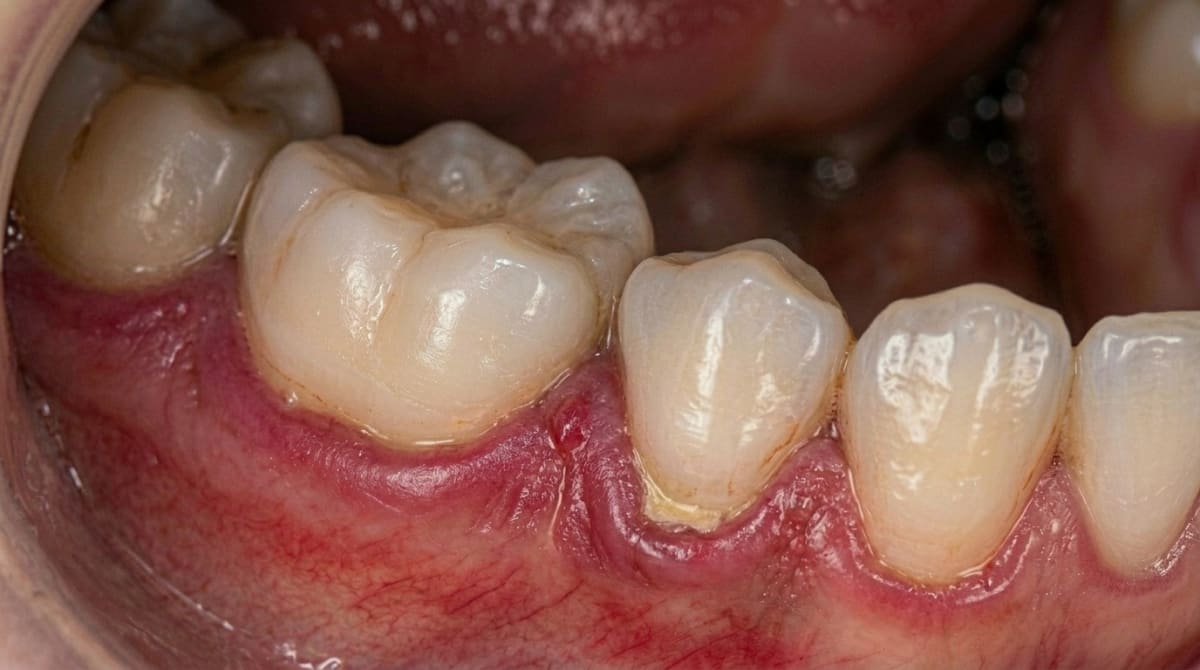

Gum bleeding is usually a sign of inflammation caused by bacteria in plaque. When plaque is not removed regularly, it irritates the gum tissue and causes it to swell and bleed. A landmark study by Löe et al. (1965) first demonstrated that plaque accumulation directly causes gingivitis, and that removing the plaque reverses the condition.

Plaque and tartar buildup: The primary cause. When plaque hardens into tartar (calculus), it can only be removed by a dental professional

Old or overhanging fillings: Rough edges on old dental work can trap food and bacteria against the gum line

These could be signs that plaque has hardened into tartar, which can only be removed with professional cleaning. A deep cleaning (scaling and root planing) removes bacteria and tartar from below the gum line, giving your gums a chance to heal and reattach to the teeth.